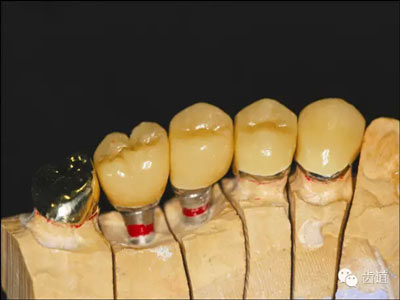

技工室

如果醫(yī)生將上HE架的工作交給了技工室,那么有關(guān)咬合記錄的工作就結(jié)束了,之后的步驟由技工室完成 。對(duì)于那些自己上HE架的醫(yī)生,我們來進(jìn)一步說明怎么進(jìn)行下面的步驟。將平板電腦放置于底座,并放置于模型前方大約6-12英寸,啟動(dòng)軟件。將上頜模型放置于HE架的上頜體上(圖10)。調(diào)出之前拍攝的患者照片。

10.jpg

圖10:模型照片

調(diào)整上頜模型的傾斜度,使之與圖像上的各個(gè)標(biāo)志點(diǎn)位置重合。確認(rèn)中線,切嵴,HE平面與面部參考點(diǎn)的位置(圖11)。

將模型調(diào)整到正確位置后,拍攝一張照片。如果需要,可以對(duì)所拍攝照片調(diào)整大小和位置,然后保存。通過調(diào)整面部照片和上頜模型照片的透明度,可以再次確認(rèn)上頜模型的位置是否正確,然后將上頜模型固定于HE架上的上頜體。打開有關(guān)咬合關(guān)系的記錄(圖9),并據(jù)此將下頜模型放置于正確的位置,然后在HE架上固定?! ?/p>

此時(shí),VF軟件中有了三張圖像,一張是顱面部的參考圖像,一張是患者的面部照片,還有一張是上頜模型的照片。通過調(diào)整任何一張圖片的透明度,進(jìn)一步確認(rèn)三者之間位置的正確性(圖12),從而保證最終上頜模型在HE架上處于正確的位置。技工室的操作部分到此也就全部完成了(圖13)。在視頻網(wǎng)站YouTube上有相關(guān)的操作視頻,可以查看(圖14)。

12.jpg

圖12:顱面部參考圖像,患者面部照片和上頜模型照片重疊的截屏

13.jpg

圖13:VF軟件指導(dǎo)下完成的模型上HE架